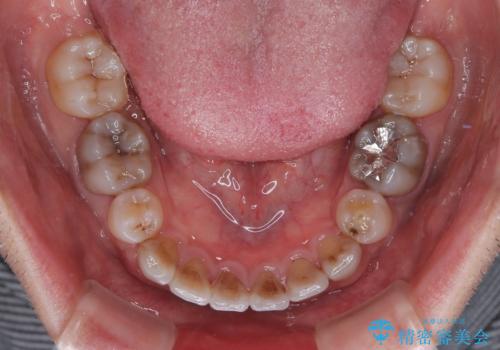

- 口元の突出感を改善するための抜歯矯正を終えた患者様ですが、幼少期からの変色した歯をセラミッククラウンにて自然な色合いに変えていくこととしました。

口を開けたときに目につく範囲を希望されたため上下ともに8本ずつをオールセラミッククラウンによる補綴治療を行うこととしました。

近年では大変珍しいですが、胎児あるいは乳幼児期の抗生物質の影響で永久歯が変色してしまうことがあります。

ホワイトニングでの改善は期待できないため、オールセラミッククラウンによる補綴治療が必要となります。